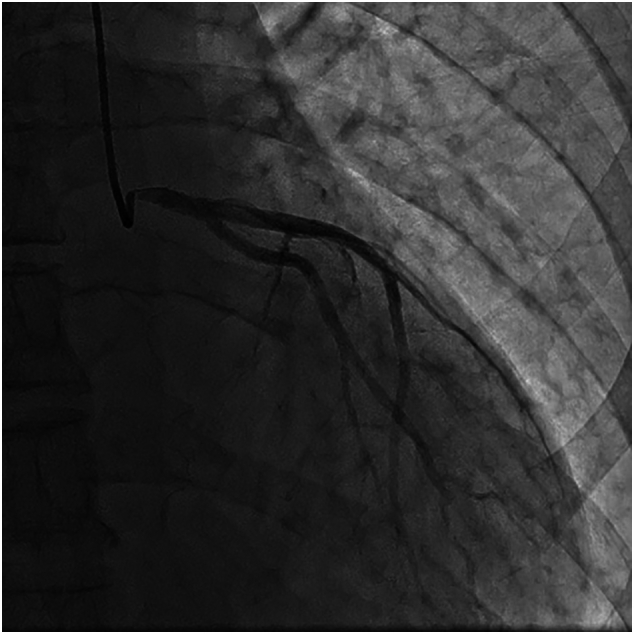

Fig. 2.

Case #1. Coronary angiography revealed subtotal stenosis of the RCA.

Case #2. Coronary angiography revealed 90% ostial stenosis of the RCA.